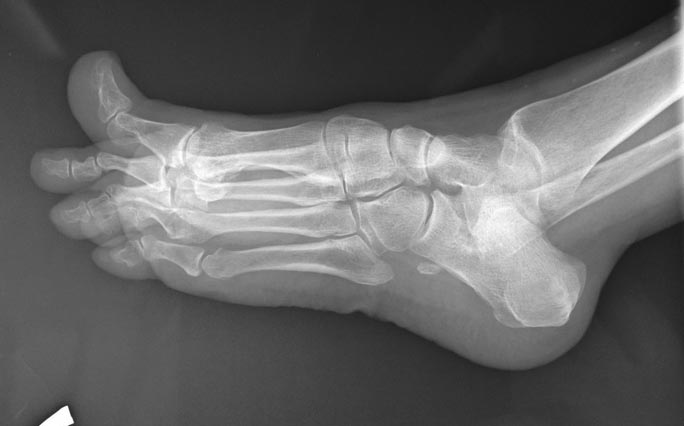

Пциентка Н, 58 лет. Больна с 2005г. Лечилась консервативно. Со слов,

тогда было сильное искривление 1,2,3,4 пальцев в латеральную сторону.

В 2012г. операция: коррекция деформаций 1,2,3, 4 пальцев.Рецидив.

В 2013г. коррекция деформации 2,3,4 пальцев. С ноября

2014г. рецидив деформации 1,2,3,4 пальцев.

Возможные варианты коррекции?